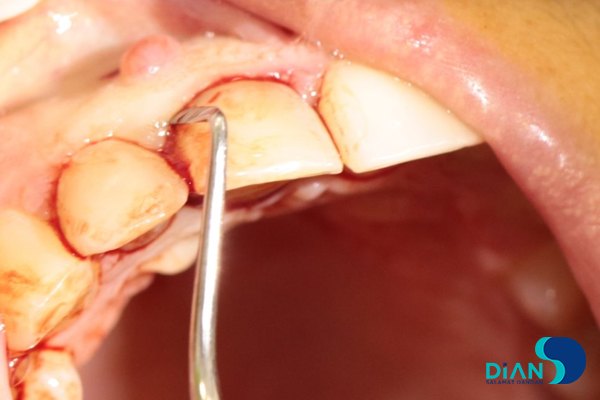

Under local anesthesia of DS-Forte articaine 4% the dentist made syndesmotomy and removed artificial tooth crown.

The root of the tooth root was divided into vestibular and palatal fragments.

In the process of vestibular root fragment extraction the dentist found its interlocking with alveolar socket. There was a risk that a root fragment would break off with a part of alveolar socket. It was decided to apply «Socket shield» technique. The palatal root fragment was removed.

Then the dentist polished remained root part and conducted alveoli curettage.